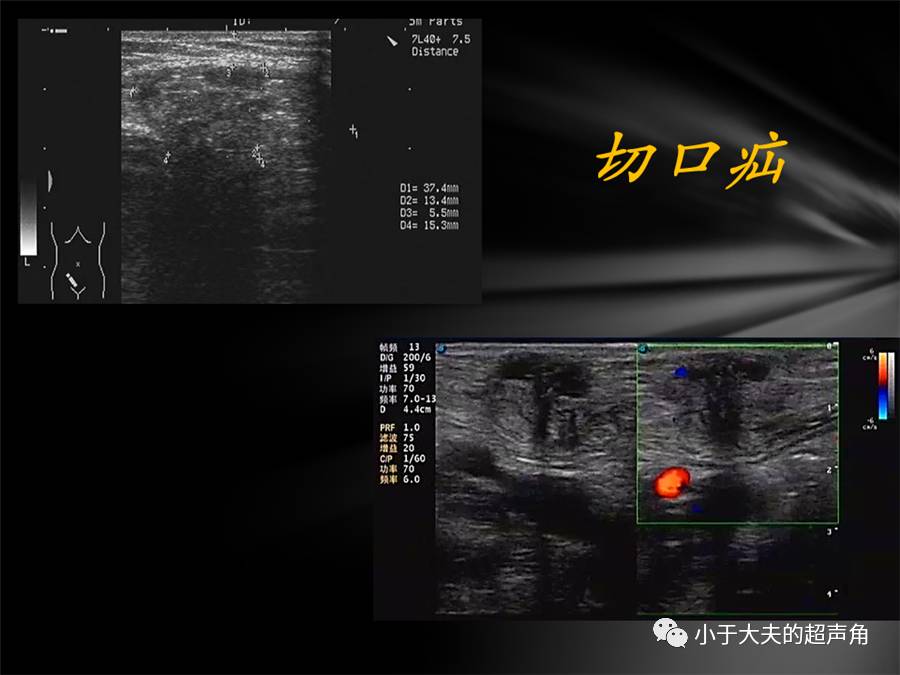

上图:果然,在紧邻肠管的既往手术切口处肌层内,发现不规则偏低回声,大小约4.2×3.0cm,边界模糊不清。

上图:CDFI:偏低回声内未见明显血流信号。

上图:既往切口深方另一处占位,边界模糊不清,内部回声减低不均。

上图:CDFI:内部也未探及明显血流信号。